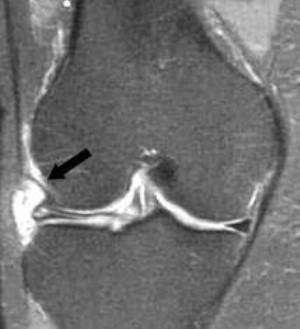

Окончательное диагностирование проводят по результатам пальпации, артроскопического и ультразвукового исследования либо магнитно-резонансной томографии коленного сустава. При образовании деформирующего артроза мыщелка тибиальной кости проявляются характерные признаки на рентгенографических снимках (симптом Раубера-Ткаченко).